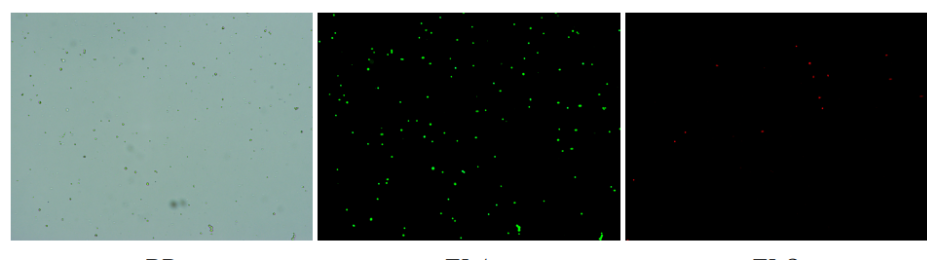

人肝癌樣本,懸液背景干凈,活性91.69%,結(jié)團率6%